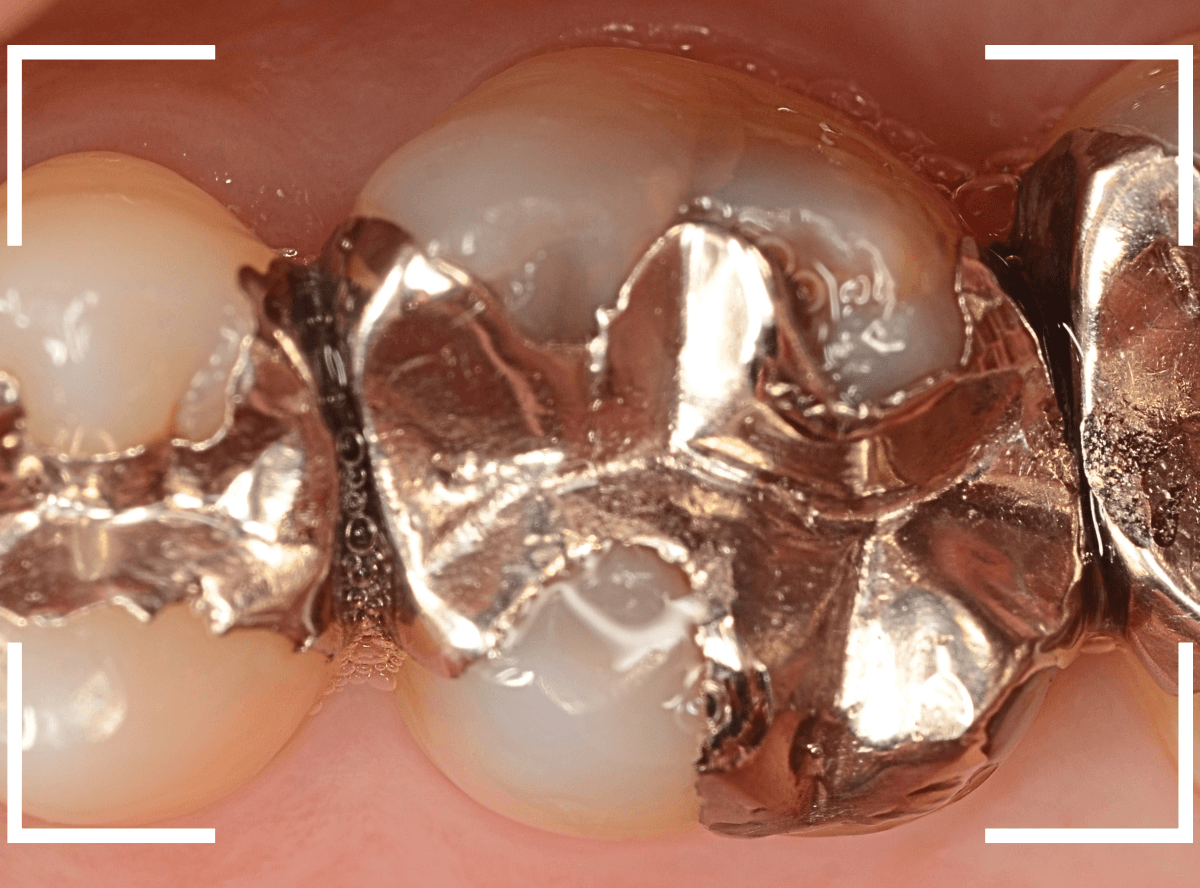

Case.16 金属の周りであちこちから虫歯

検診を希望された患者さんのケースです。

お口の中を拝見すると、上の奥歯の歯のすき間(隣接面)や、変色したレジンの中が怪しい感じです。

レントゲン写真で確認します。

青い線が神経で、赤い線が虫歯と思われる部分です。

奥から3歯が虫歯と思われますが、特に中央の歯の虫歯が深そうです。

まず、中央の歯の金属を除去します。

〇部分は前の治療時にしいたセメントです。この下に虫歯が広がっていると思われます。

セメントを除去したところです。

赤く染め出されているところが虫歯です。

神経に近くなっていますので、診療に虫歯を除去します。

側面のレジンや隣の歯との間の虫歯も慎重に除去します。

かなり広く虫歯が広がっています。

奥の歯の虫歯も全て除去しました。

3歯すべての虫歯を除去したところです。

しばらくお薬をつめて症状を経過観察した後、型どりをしてつめものを再製作する予定です。